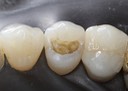

Scott Kanamori #15

Scott Kanamori #15 finish

Scott Kanamori #15 buccal view